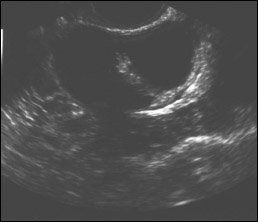

Ultrasound images of a single thin septated cyst (top); a single thick septated cyst (middle); and multiple septated cysts (bottom). Image courtesy of Edward J. Pavlik, director of research in gynecologic oncology, UK Ovarian Screening Research Program.